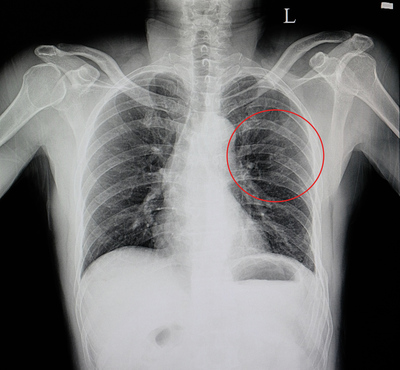

Дело было на Украине в 2002м часть называть понятно не буду, дедушки разжились бухлом, и по синему делу решили поучить жизни молодых, а так как я был из особо отличившихся, то и били меня с большим пристрастием чем остальных. В общем в одну не самую прекрасную январскую ночь, меня разбудил один из моих сослуживцев, уже прошедший экзекуцию, и я пошел в туалет, где меня уже ждали, 20 человек, бухих и скажем так, имеющие на меня зуб (это отдельная история...). Конечно прям так как на видео, лежачего не били, но... двое держат за руки спиной к стене, при этом каждый по очереди бьёт кулаком в грудь, отдельно запомнился старший сержант Сахаров - замок службы обеспечения. Я четко помню только первые два круга, третий круг уже как в тумане, помню только две мысли - молил потерять сознание, и если выживу, положу всех... Ни тому, ни другому не суждено было сбыться, хоть и не все помню, но до койки добрел сам, будить следующего не стал. Утром на зарядке пробежал 3км (перед пробежкой стянул грудь ремнями взятыми у друзей с моего призыва) брусья понятно я уже не осилил. На зарядке с нами был дежурный по части, он и инициировал телесную проверку, на которой всплыла моя грудная клетка сине-багрового цвета (мама мне в армию дала нательный крестик, оттиски от него были прямо по всей груди). Сначала меня отправили в районную, гражданскую больницу, потом ЧП разрослось аж до Генштаба, приехала проверка, полетели должности, меня отправили в окружной госпиталь, где я пролечился аж 2 дня и меня вернули обратно в часть. Дело замялось, меня лечили витаминками и йодными сеточками... Пока я отлеживался в санчасти, вся эта компания дембельнулась, и я слава богу не успел взять грех на душу (я был готов, и это чувство ненависти и бессильной ярости до сих пор со мной). Я выжил, не смотря ни на что, к переломам ребер (если правильно помню, в количестве 8-ми штук), в окружном госпитале добавили ушиб сердца, пневмоторакс и кровь в перикарде, доктор говорил, что скорее всего нужна будет операция. Служба осталась в далеком прошлом, я вспоминаю о ней даже с щемящей тоской (о плохом как-то и не вспоминается), но блядь... Отдать долг родине... Как я в свои 20 лет успел так задолжать, чтобы отдавать его такой ценой???